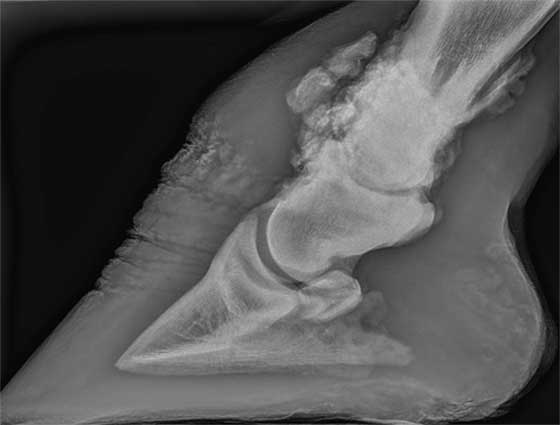

Hoefkatrol, spat, artrose,… er bestaat een krachtige oplossing voor chronische ernstige pijn wanneer alle herstelkansen voorbij zijn: BackSound®.

BackSound® is een neuromodulatietechniek waarbij we de pijn in het been van het paard onderdrukken. Deze techniek is afkomstig uit de humane geneeskunde en wordt bijvoorbeeld toegepast bij chronische facetaire rugpijn. Aangezien de uitvoering chirurgisch millimeterwerk is, wordt deze techniek echogeleid uitgevoerd en met een CRInfuus om mooi stil te staan. Gelukkig kunnen we dit op het rechtstaande paard uitvoeren.

- Hoefkatrolontsteking

- Artrose

- Verkalkingen

- Gewrichtsontstekingen

- Chronische hoefbeenfracturen

- Verbeende hoefkraakbeenderen

- Chronische aanhechtingsproblemen

- Botresorptie

- Vergroeiingen

- Kraakbeenblessures